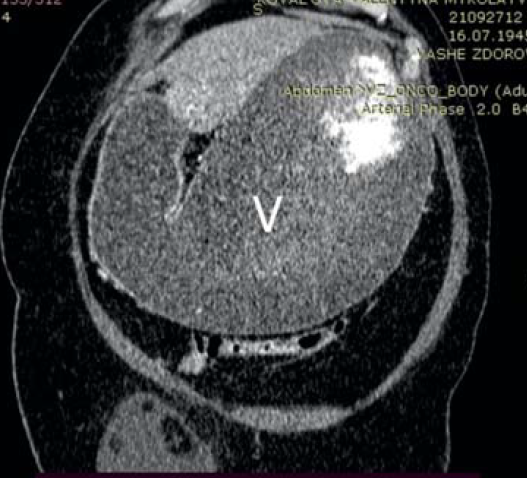

Пациентка, 76 лет, поступила в клинику с жалобами на рвоту съеденной накануне пищей, тяжесть, вздутие в верхних отделах живота, потерю веса, слабость. Из анамнеза – болеет около 3 недель, ранее неоднократно отмечала приступы боли в правом подреберье. При поступлении отмечались вздутие верхних отделов живота, наличие шума «плеска», признаки обезвоживания – сухость и дряблость кожных покровов, явления олигурии. Больная обследована. По данным КТ области брюшной полости в нисходящей ветви двенадцатиперстной кишки определяется слоистый конкремент размерами до 31×25 мм. Стенки нисходящего отдела двенадцатиперстной кишки утолщены, наружный контур нечеткий. Окружающая жировая клетчатка инфильтрирована, в т.ч. между головкой поджелудочной железы и кишкой. Желудок значительно растянут содержимым (рис. 5, 6). Лабораторно обращали на себя внимание явления гиперкоагуляции наряду с повышением уровня эритроцитов и гемоглобина (178×1012/л и 5,86 г/л соответственно), дисэлектролитными расстройствами.

Рис. 5. Компьютерная томограмма, аксиальная проекция: билиарный конкремент (стрелка), обтурирующий просвет двенадцатиперстной кишки в нисходящей части; аэробилия; желудок, растянутый содержимым (V)

Рис. 6. Компьютерная томограмма, фронтальная проекция: выраженное расширение желудка (V) на фоне обтурации двенадцатиперстной кишки конкрементом